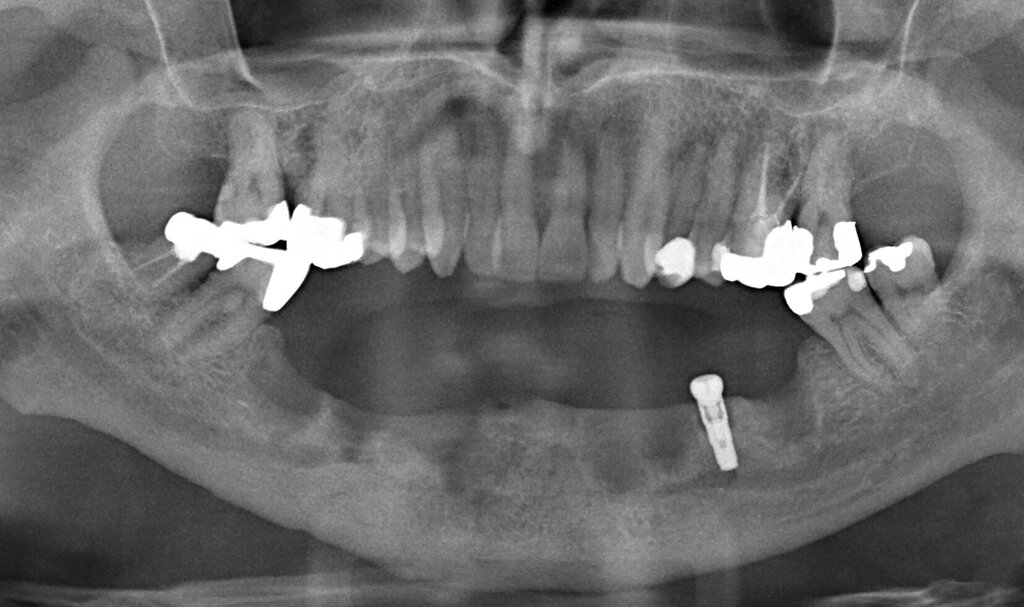

Ursprünglich waren bei dieser Patientin nach einem Frontzahntrauma vier Implantat-gestützte Kronen geplant. Nach dem frühen Verlust des Implantats in regio 21 während der Einheilzeit wurde dann eine auf drei Implantaten abgestützte Brücke eingegliedert. Das bestehende vertikale und horizontale Weichgewebsdefizit wurde bei der verschraubten Implantatbrücke durch aufgebrannte rosafarbene Keramik kaschiert (Abb. 3a). Funktionell war die Brückenversorgung über viele Jahre erfolgreich und zeigte keinerlei Lockerungsgrad. Trotz guter Mundhygiene war in Kontrollsitzungen ein kontinuierlicher Knochenabbau an allen Implantaten festzustellen (Abb. 3b). Zur Vermeidung eines weiteren Knochenverlusts fiel circa 15 Jahre nach der Erstversorgung die Entscheidung zur Explantation. Zu diesem Zeitpunkt war die Patientin 55 Jahre alt.

Nach dem Abschrauben der Suprastruktur (Abb. 3c und 3d) wurden alle Implantate unter Lokalanästhesie mit einem passenden Trepanbohrer umbohrt und ohne Lappenbildung entfernt. Die temporäre Lückenversorgung erfolgte mit einer herausnehmbaren Prothese, die über Gussklammern am Restgebiss abgestützt war.

Da sechs Monate nach der Explantation keine nennenswerte knöcherne Regeneration festzustellen war, wurde eine zweizeitige Implantation nach Knochenaugmentation mithilfe dünner Knochenscheiben aus dem Kieferwinkel geplant. Die Entnahme erfolgte mit oszillierenden Instrumenten (Piezosurgery). Der Knochenblock wurde in dünne Scheiben geschnitten und mit Osteosyntheseschrauben am Alveolarfortsatz fixiert (Abb. 3e). Darüber wurden die Weichgewebe dicht vernäht. Weitere fünf Monate später erfolgte die Schraubenentfernung und die Implantation von zwei Bone-Level-Implantaten in regio 12 und 22 mit geschlossener Einheilung (Abb. 3f und 3g). Bei der Implantatfreilegung weitere sechs Monate später wurden die Weichgewebsdefizite im Brückengliedbereich durch ein kombiniertes Bindegewebs-/Schleimhauttransplantat aufgefüllt und gleichzeitig die keratinisierte periimplantäre Gingiva und Alveloarmukosa verbreitert (Abb. 3h und 3i). Die prothetische Versorgung erfolgte erst weitere drei Monate später, nach dem Konsolidieren der Weichgewebe. Die umfangreichen Augmentationsmaßnahmen konnten das transversale Weichgewebsdefizit vollständig kompensieren, während das verbleibende vertikale Defizit zu zervikal etwas längeren Kronen und Brückengliedern führte. Aufgrund der guten Abdeckung durch die Oberlippe kann das ästhetische Ergebnis als zufriedenstellend bewertet werden (Abb. 3j bis 3l).